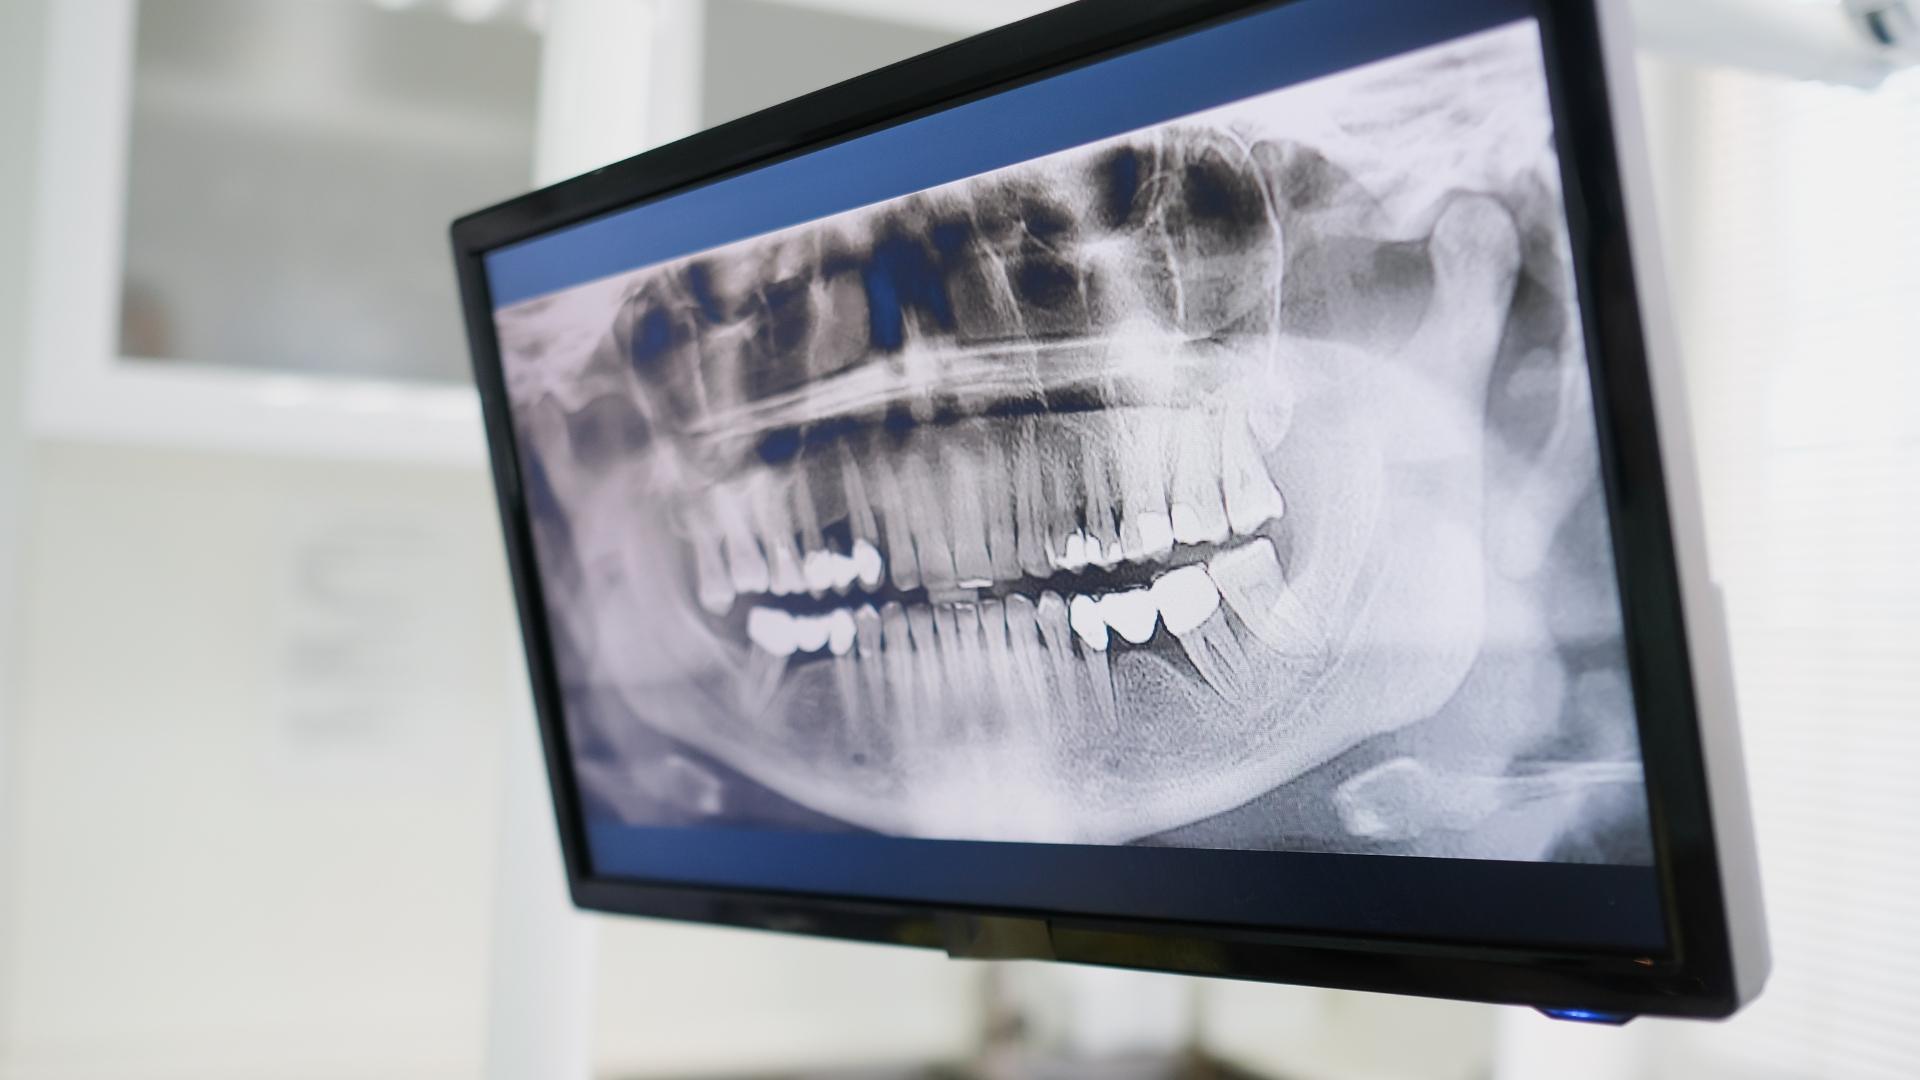

Zdjęcie rentgenowskie to podstawowe badanie wykorzystywane we współczesnej stomatologii. W profesjonalnej pracowni RTG wykonujemy zdjęcia rentgenowskie Tomografem Carestream CS 8100 3D, które są wykorzystywane w diagnostyce stomatologicznej oraz służą do zaplanowania leczenia.

Ortopantomograficzne, inaczej OPG - obrazuje wszystkie zęby, stawy skroniowe i zatoki